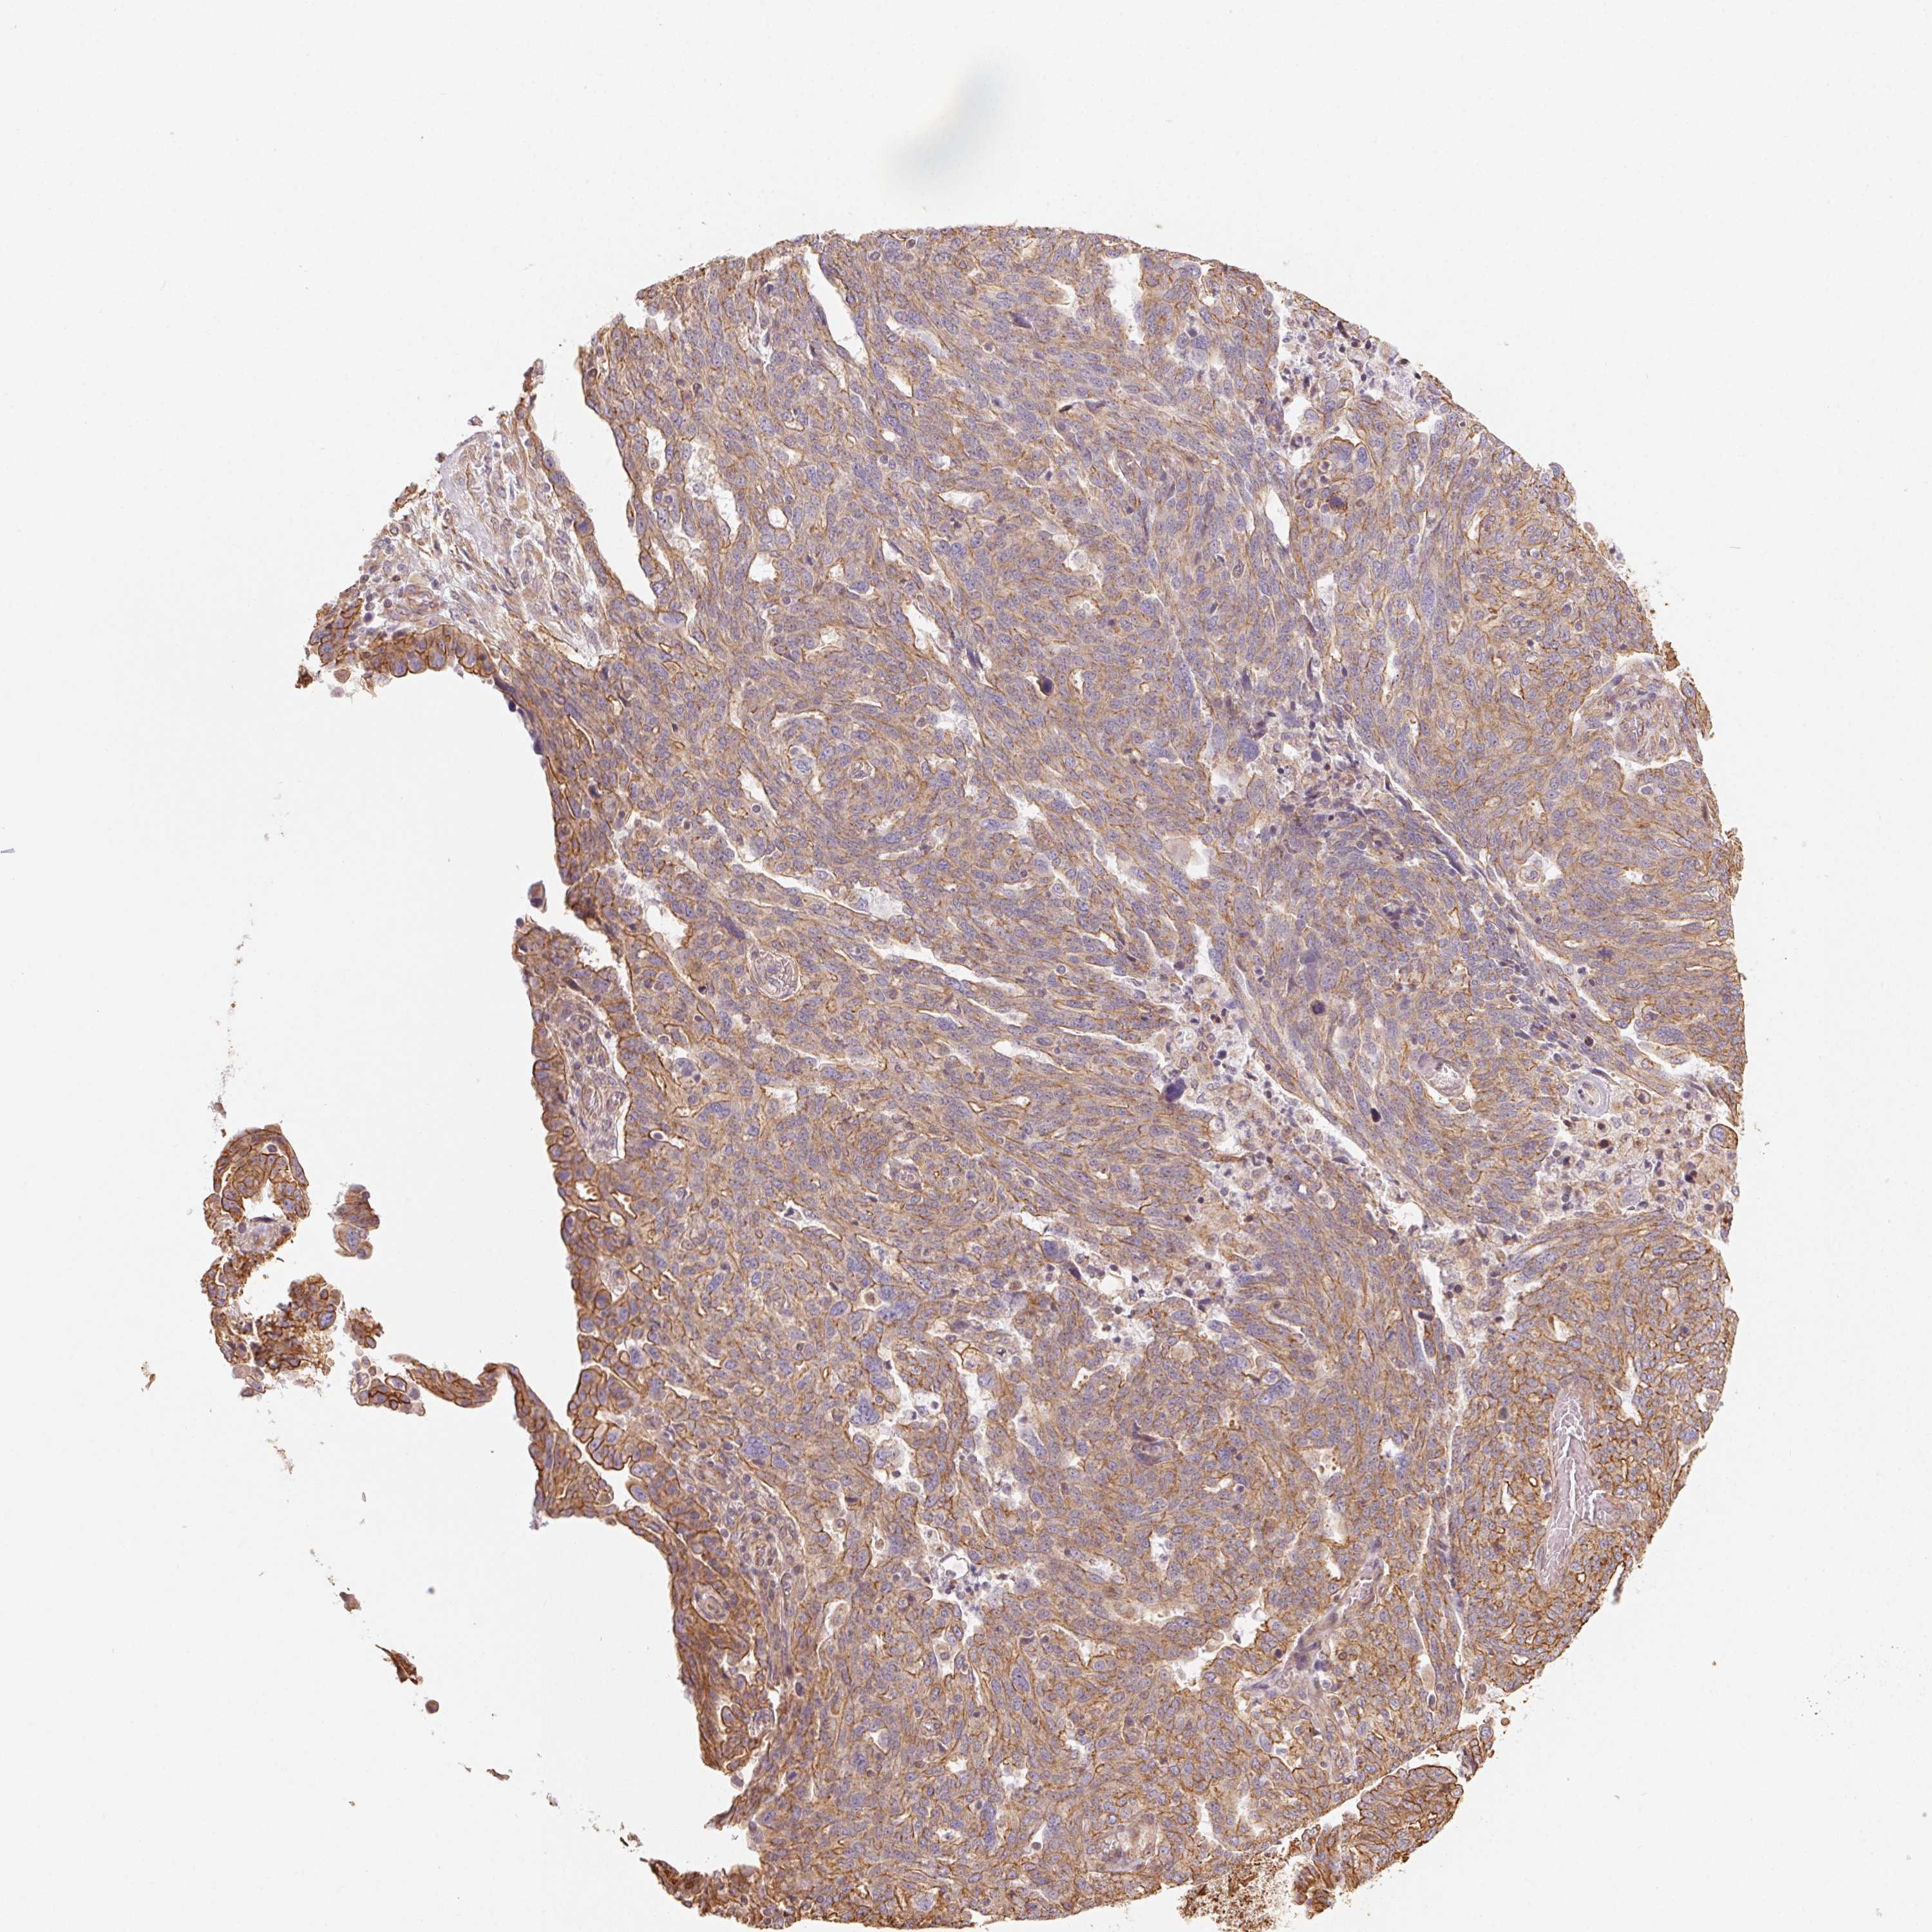

OVARIAN CANCER - Protein expressioni

A mouse-over function shows sample information and annotation data. Click on an image to view it in a full screen mode. Samples can be filtered based on level of antibody staining by selecting one or several of the following categories: high, medium, low and not detected. The assay and annotation is described here.

Note that samples used for immunohistochemistry by the Human Protein Atlas do not correspond to samples in the TCGA dataset.

Antibody stainingi

Antibody staining in the annotated cell types in the current human tissue is reported as not detected, low, medium, or high, based on conventional immunohistochemistry profiling in selected tissues. This score is based on the combination of the staining intensity and fraction of stained cells.

Each image is clickable and will lead to virtual microscopy that enables deeper exploration of all samples and also displays staining intensity scores, fraction scores and subcellular localization as well as patient and tissue information for each sample.

Antibody HPA056752

Cystadenocarcinoma, serous, NOS

Cystadenocarcinoma, mucinous, NOS

Carcinoma, endometroid